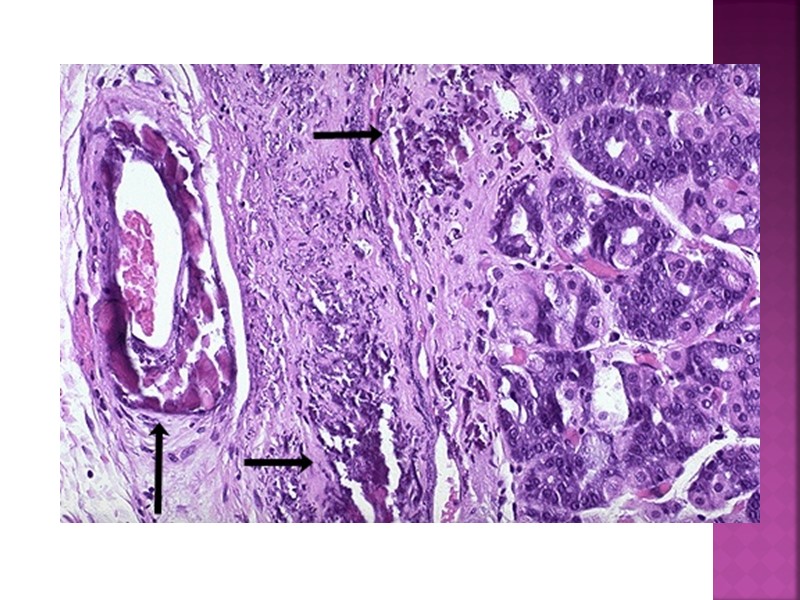

Дистрофия (греч. dys –приставка, обозначающая расстройство и trophe – питание) – сложный патологический процесс, в основе которого лежат метаболические нарушения, приводящие к структурным изменениям. В морфологическом отношении: 1) появление веществ, которых в норме нет или содержится мало, 2) исчезновение из клеток и тканей присущих для них веществ

морфогенетические механизмы Инфильтрация – это избыточное проникновение продуктов обмена из крови и лимфы в клетки или межклеточное вещество с последующим их накоплением (атеросклероз). Декомпозиция или фанероз – это распад ультраструктур клеток и межклеточного вещества, ведущий к нарушению тканевого или клеточного метаболизма и накоплению продуктов нарушенного обмена в ткани или клетке, (жировая дистрофия при дифтерийной интоксикации кардиомиоцитов. Извращенный синтез – это синтез веществ в клетках и тканях, которые не встречаются в норме (амилоидоз) Трансформация – образование продуктов одного вида обмена вместо продуктов другого вида обмена (трансформация компонентов жиров и углеводов в белки).

Паренхиматозные дистрофии: 1 ) Белковые - зернистая - гидропическая - гиалиново-капельная - роговая 2 ) Жировые 3) Углеводные -с нарушением обмена гликогена -с нарушением обмена гликопротеидов

Мезенхимальные дистрофии: Белковые: мукоидное набухание, фибриноидное набухание, гиалиноз, амилоидоз. Жировые – общее ожирение, кахексия Углеводные. Характерно ослизнение тканей : кахексия, недостаточность эндокринных желез (микседема), мукополисахаридозы (наследственные заболевания).

Гиалиноз -общий -местный -гиалиноз сосудов -гиалиноз собственно соединительной ткани.

Гиалиноз возникает в исходе: - фибриноидного набухания - плазматического пропитывания - склероза